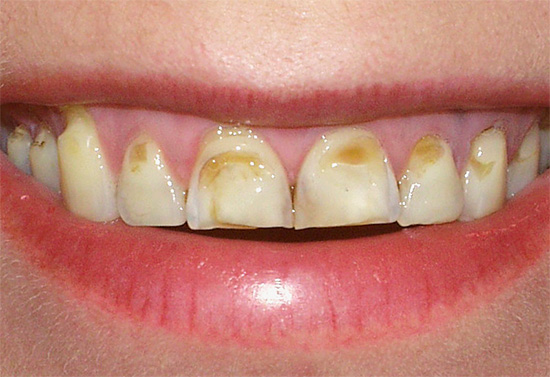

Tuttavia, il pericolo principale e più reale della carie durante la gravidanza è la possibilità del suo passaggio a una forma acuta, un grave danno a molti denti contemporaneamente e la loro perdita da parte di una donna in un tempo abbastanza breve. In altre parole, la carie è di solito più pericolosa per la madre che per il feto.

- La carie si trova nel 91,4% delle donne in gravidanza normale e nel 94% con tossicosi.

- L'intensità media del danno ai denti nelle donne in gravidanza va da 5,4 a 6,5 (questo è un livello elevato);

- Iperestesia dello smalto (ipersensibilità) è osservata nel 79% delle donne durante la gestazione.